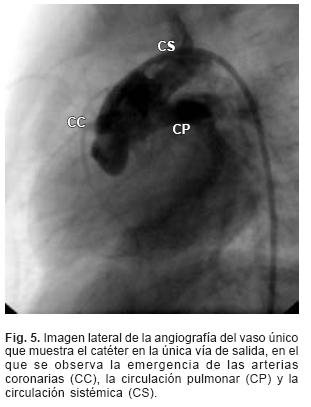

En el cateterismo cardíaco, el angiograma en atrio derecho mediante inyección en vena cava superior mostró ausencia de conexión atrioventricular derecha, con flujo de atrio derecho a atrio izquierdo a través de una comunicación interatrial y a través de la válvula mitral sin insuficiencia al ventrículo izquierdo. El angiograma en ventrículo izquierdo mostró la conexión ventriculoarterial a través de un vaso único con cabalgamiento del 10% sobre el septum interventricular hacia el lado derecho y a través de una comunicación interventricular la opacificación del ventrículo derecho, sin vía de entrada. El angiograma en tronco común mostró válvula troncal sin insuficiencia con tres ostiums coronarios por origen independiente de la arteria coronaria descendente anterior y la circunfleja y un ostium coronario derecho, en el tronco común la emergencia de un tronco pulmonar con bifurcación en ambas ramas pulmonares, sin obstrucción en su origen.